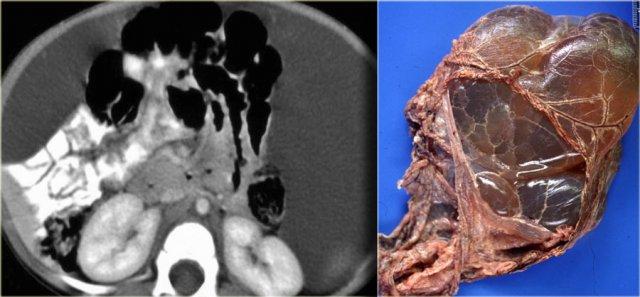

Nang Mạc Treo – U Mạch Bạch Huyết

Nang mạc treo là thuật ngữ mô tả dùng để chỉ bất kỳ tổn thương dạng nang nào nằm trong mạc treo.

Thông thường đây là u mạch bạch huyết (lymphangioma).

U mạch bạch huyết là tổn thương lành tính có nguồn gốc mạch máu.

Phần lớn u mạch bạch huyết nằm ở vùng cổ, nhưng 5% có vị trí trong ổ bụng.

U mạch bạch huyết có các vách ngăn ngấm thuốc.

Khác với di căn phúc mạc dạng nang, cổ trướng không phải là đặc điểm của u mạch bạch huyết.

Khi thấy một tổn thương dạng nang có vách ngăn mà không có cổ trướng, chẩn đoán có khả năng nhất là u mạch bạch huyết.

U mạch bạch huyết thường có liên quan mật thiết với ruột non.

Trong phẫu thuật, việc tách khối u ra khỏi ruột thường rất khó khăn và trong nhiều trường hợp phải cắt bỏ cả đoạn ruột liên quan.

Trường hợp bên trái cũng là u mạch bạch huyết.

Lưu ý rằng CT không phải lúc nào cũng thể hiện rõ các vách ngăn, mặc dù bệnh phẩm cho thấy rõ ràng nhiều vách ngăn.

Siêu âm hoặc MRI mô tả các vách ngăn này tốt hơn CT.